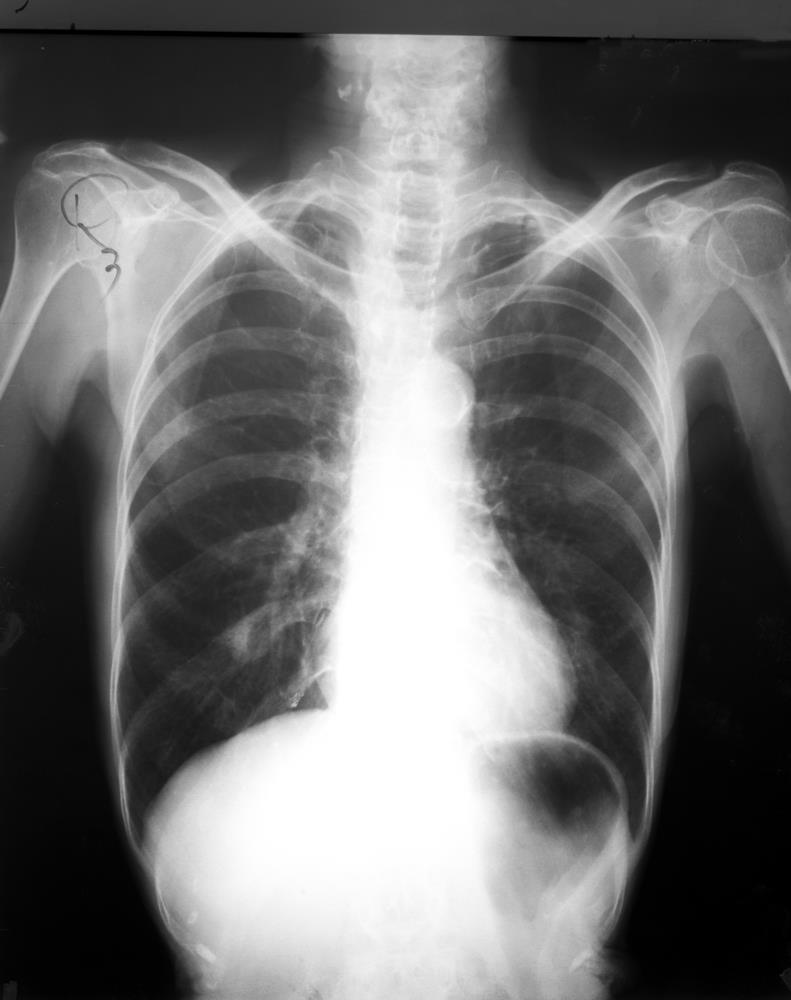

Lung cancer is a cancer that forms in tissues of the lung, usually in the cells lining the air passages. Primary Lung cancer was originally categorized simply by the size of cell - small or non-small! There are several types: